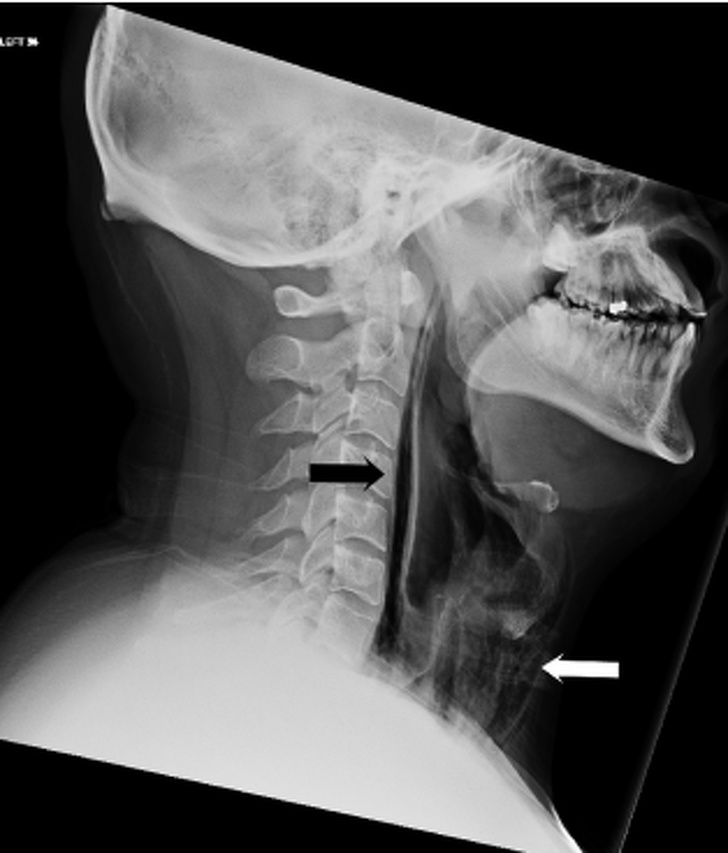

▼他閉上嘴巴、捏住鼻子,強忍著不打噴嚏,結果喉嚨破裂在醫院住了2個星期。